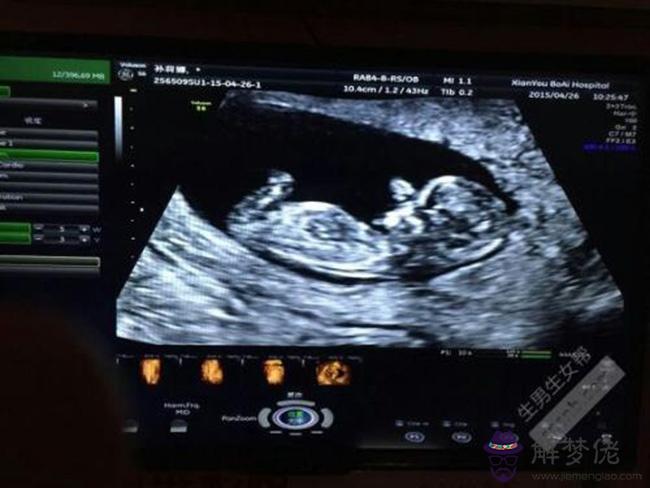

您好,您的檢查結果正常,兩個月B超檢查不能查明胎兒男女,也有規定,不能檢查胎兒性別,寶寶健康最重要,建議您注意休息,補充營養,規律做好產檢。2個月彩超圖看男孩女孩。

一般來說,懷孕16周左右也就是孕4個月時,孕婦做B超便能檢測出胎兒的性別。B超是最簡單和便捷的方法,懷孕三個月的時候,胎兒已經具有了發育良好的官,所以4個月時一般B超可以推斷出胎兒的性別。但是胎兒性別的判斷和胎位也有著很大的關系。若胎兒在母體內胎位良好,加上醫生臨床經驗豐富的話就能夠準確判斷胎兒的性別。懷孕兩個月孕囊看男女準嗎。

第一,掃描:是一種聲波,到目前為止的報告顯示,它對胎兒沒有影響,因此在婦產科界使用非常普遍。利用診斷胎兒性別時,的準確度可達95%以上,的可靠度則只有85%左右。受醫生的經驗和胎位的影響。